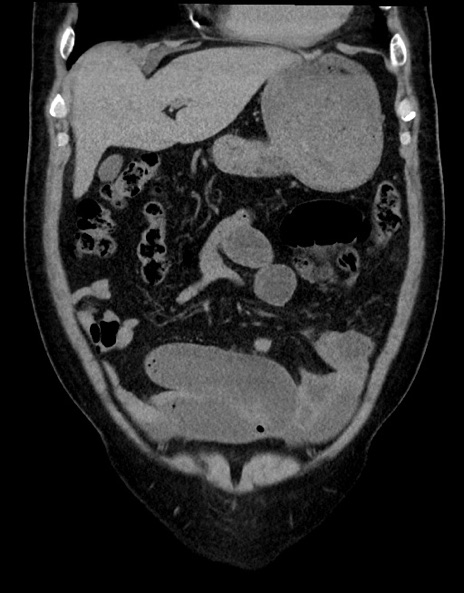

横断像

【症例】70歳代男性

【主訴】腹痛

【現病歴】今朝から腹痛あり。全体的に痛い。特に左上の方。排ガスが今日はない。冷や汗が出る。

【既往歴】直腸癌術後

【身体所見】左側腹部〜上腹部に圧痛あり。腹膜刺激症状明らかなではない。軽度反跳痛。左下腹部に術後瘢痕あり。

【データ】WBC 7700、CRP 0.02